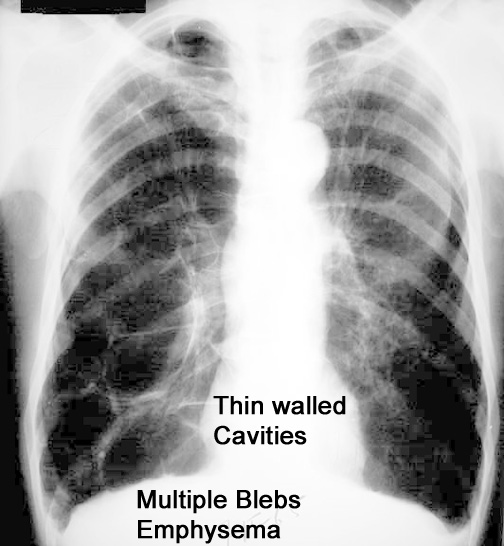

Case 1 Labeled Image What are the conditions where you get thin walled cavities?